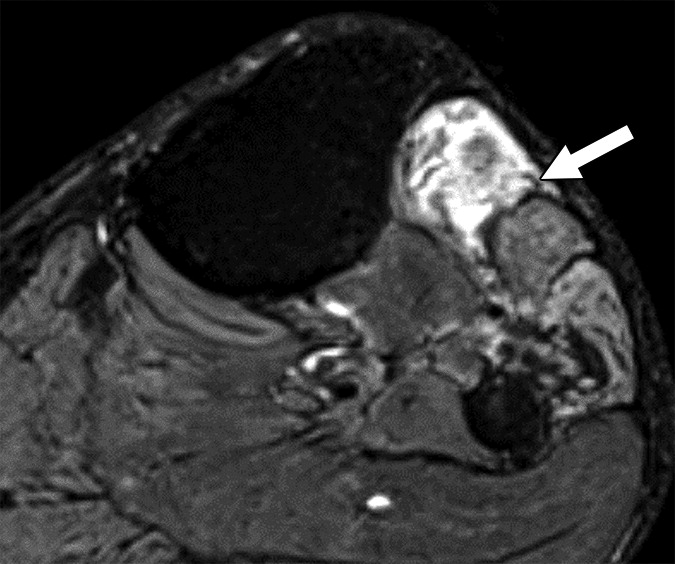

Offering a uniform lexicon and practical guideline for reporting neuropathic conditions on MRI, ultimately, NS-RADS accuracy for determining milder versus more severe categories per radiologist ranged from 88% to 97% for nerve lesions and from 86% to 94% for muscle abnormalities (Fig. 2).

On the basis of the overall promising interrater agreement shown in this study, we believe that the newly proposed NS-RADS classification will perform as well in routine practice as it did in this initial validation study (Fig. 3).